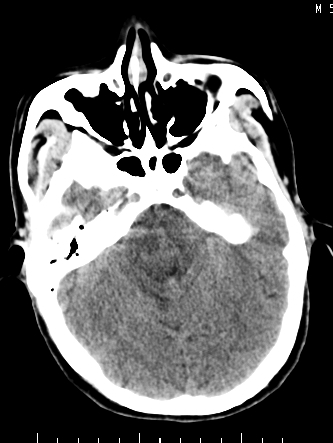

m/50,头昏头痛1月,近3天感觉左半肢体活动不利,自述半年前呈患肺tb,腰穿脑脊液未见特殊改变。现做头颅ct请大家会诊。

ct值?是囊变?梗塞软化灶形成

考虑颅内感染性病变:结核可能性大。

结核性脑膜炎,结核瘤,梗塞灶三症并存,提示颅内结核感染可能性大。

感染性病变;脑干脓肿(脓肿壁形成期),基底节及内囊(脑炎期)。顺便问一句,该病人是不是抵抗力很差,有没有糖尿病。

右侧基底节区缺血性脑梗塞.脑干区考虑结核.

可考虑结核,患者水肿范围大,囊性病灶边缘密度较高,不考虑胶质母细胞瘤